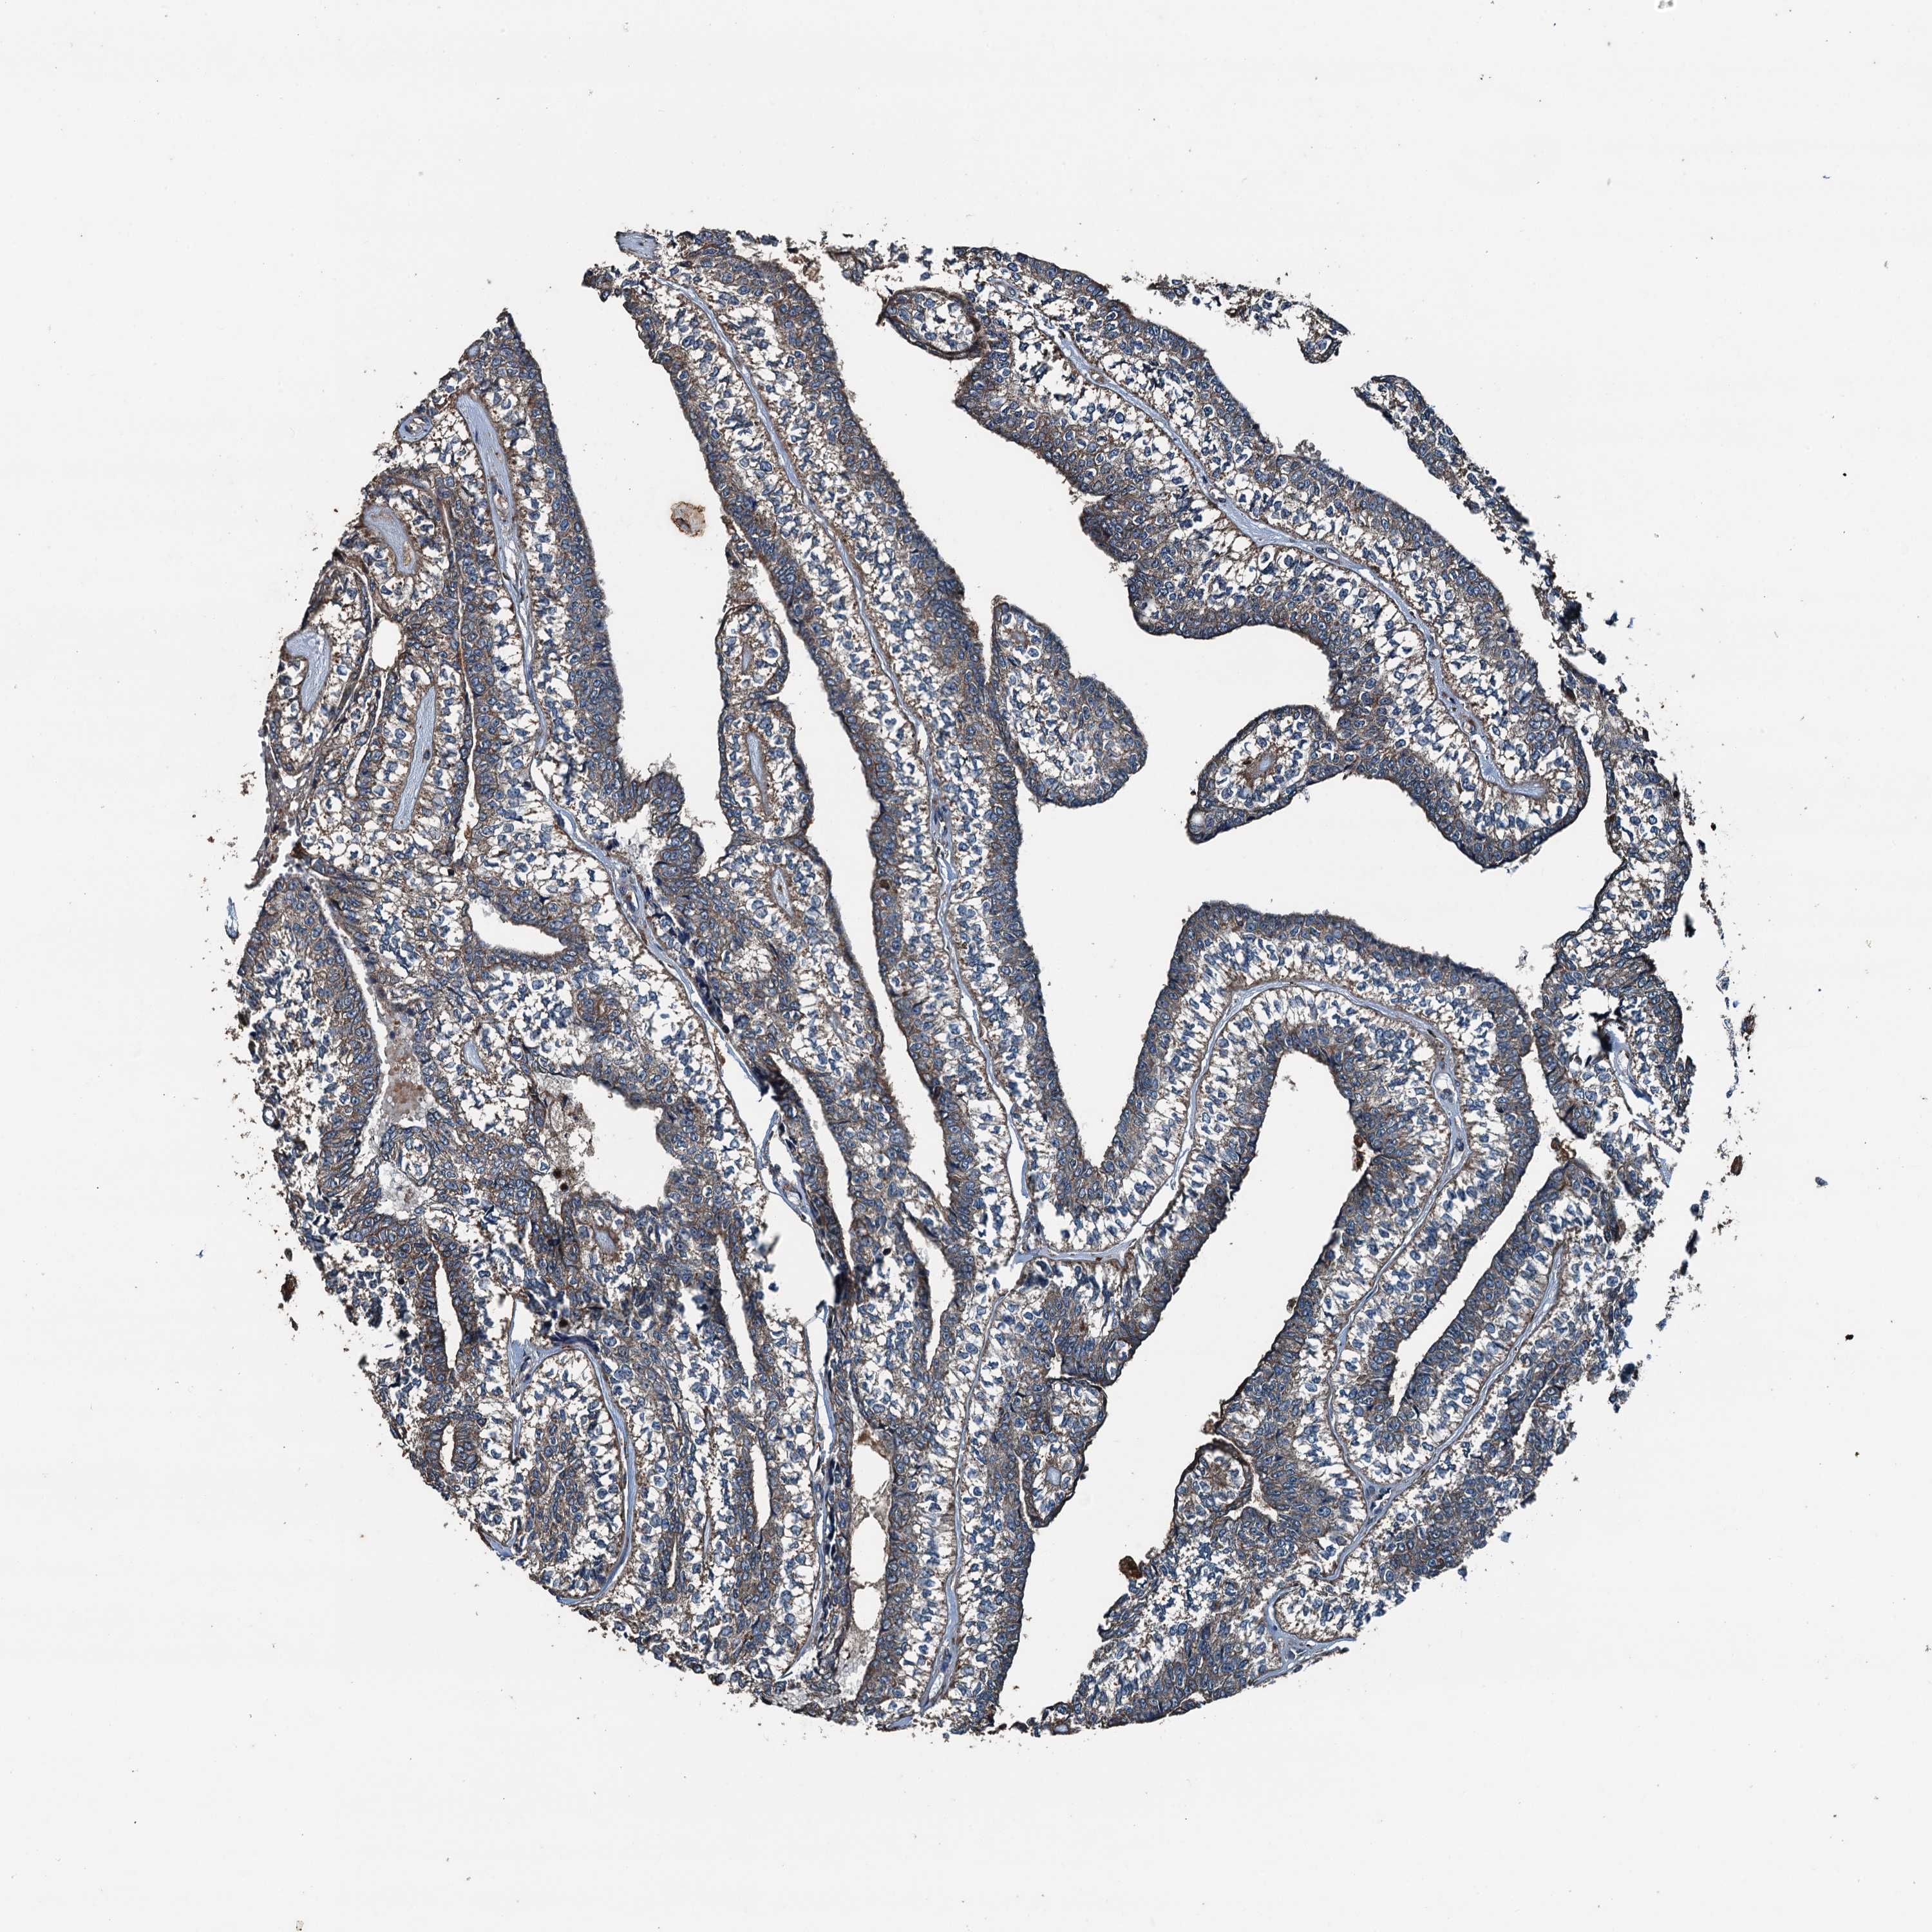

HEAD AND NECK CANCER - Protein expressioni

A mouse-over function shows sample information and annotation data. Click on an image to view it in a full screen mode. Samples can be filtered based on level of antibody staining by selecting one or several of the following categories: high, medium, low and not detected. The assay and annotation is described here.

Antibody stainingi

Antibody staining in the annotated cell types in the current human tissue is reported as not detected, low, medium, or high, based on conventional immunohistochemistry profiling in selected tissues. This score is based on the combination of the staining intensity and fraction of stained cells.

Each image is clickable and will lead to virtual microscopy that enables deeper exploration of all samples and also displays staining intensity scores, fraction scores and subcellular localization as well as patient and tissue information for each sample.

Antibody HPA041227

Staining

High

Medium

Low

Not detected

Intensity

Strong

Moderate

Weak

Negative

Quantity

>75%

75%-25%

<25%

None

Location

Nuclear

Cytoplasmic/membranous

Cytoplasmic/membranous,nuclear

Squamous cell carcinoma, NOS